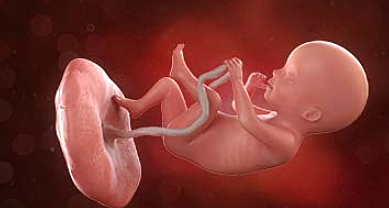

• Semana 40

Semana 40

El bebé en la semana 40 de embarazo mide entre 48 y 51 centímetros de la coronilla a las nalgas, y el peso se sitúa alrededor de los 3500 gramos.Lo que está claro es que, cuanto más nos alejemos de la fecha prevista del parto, más probable es que el bebé pese más.